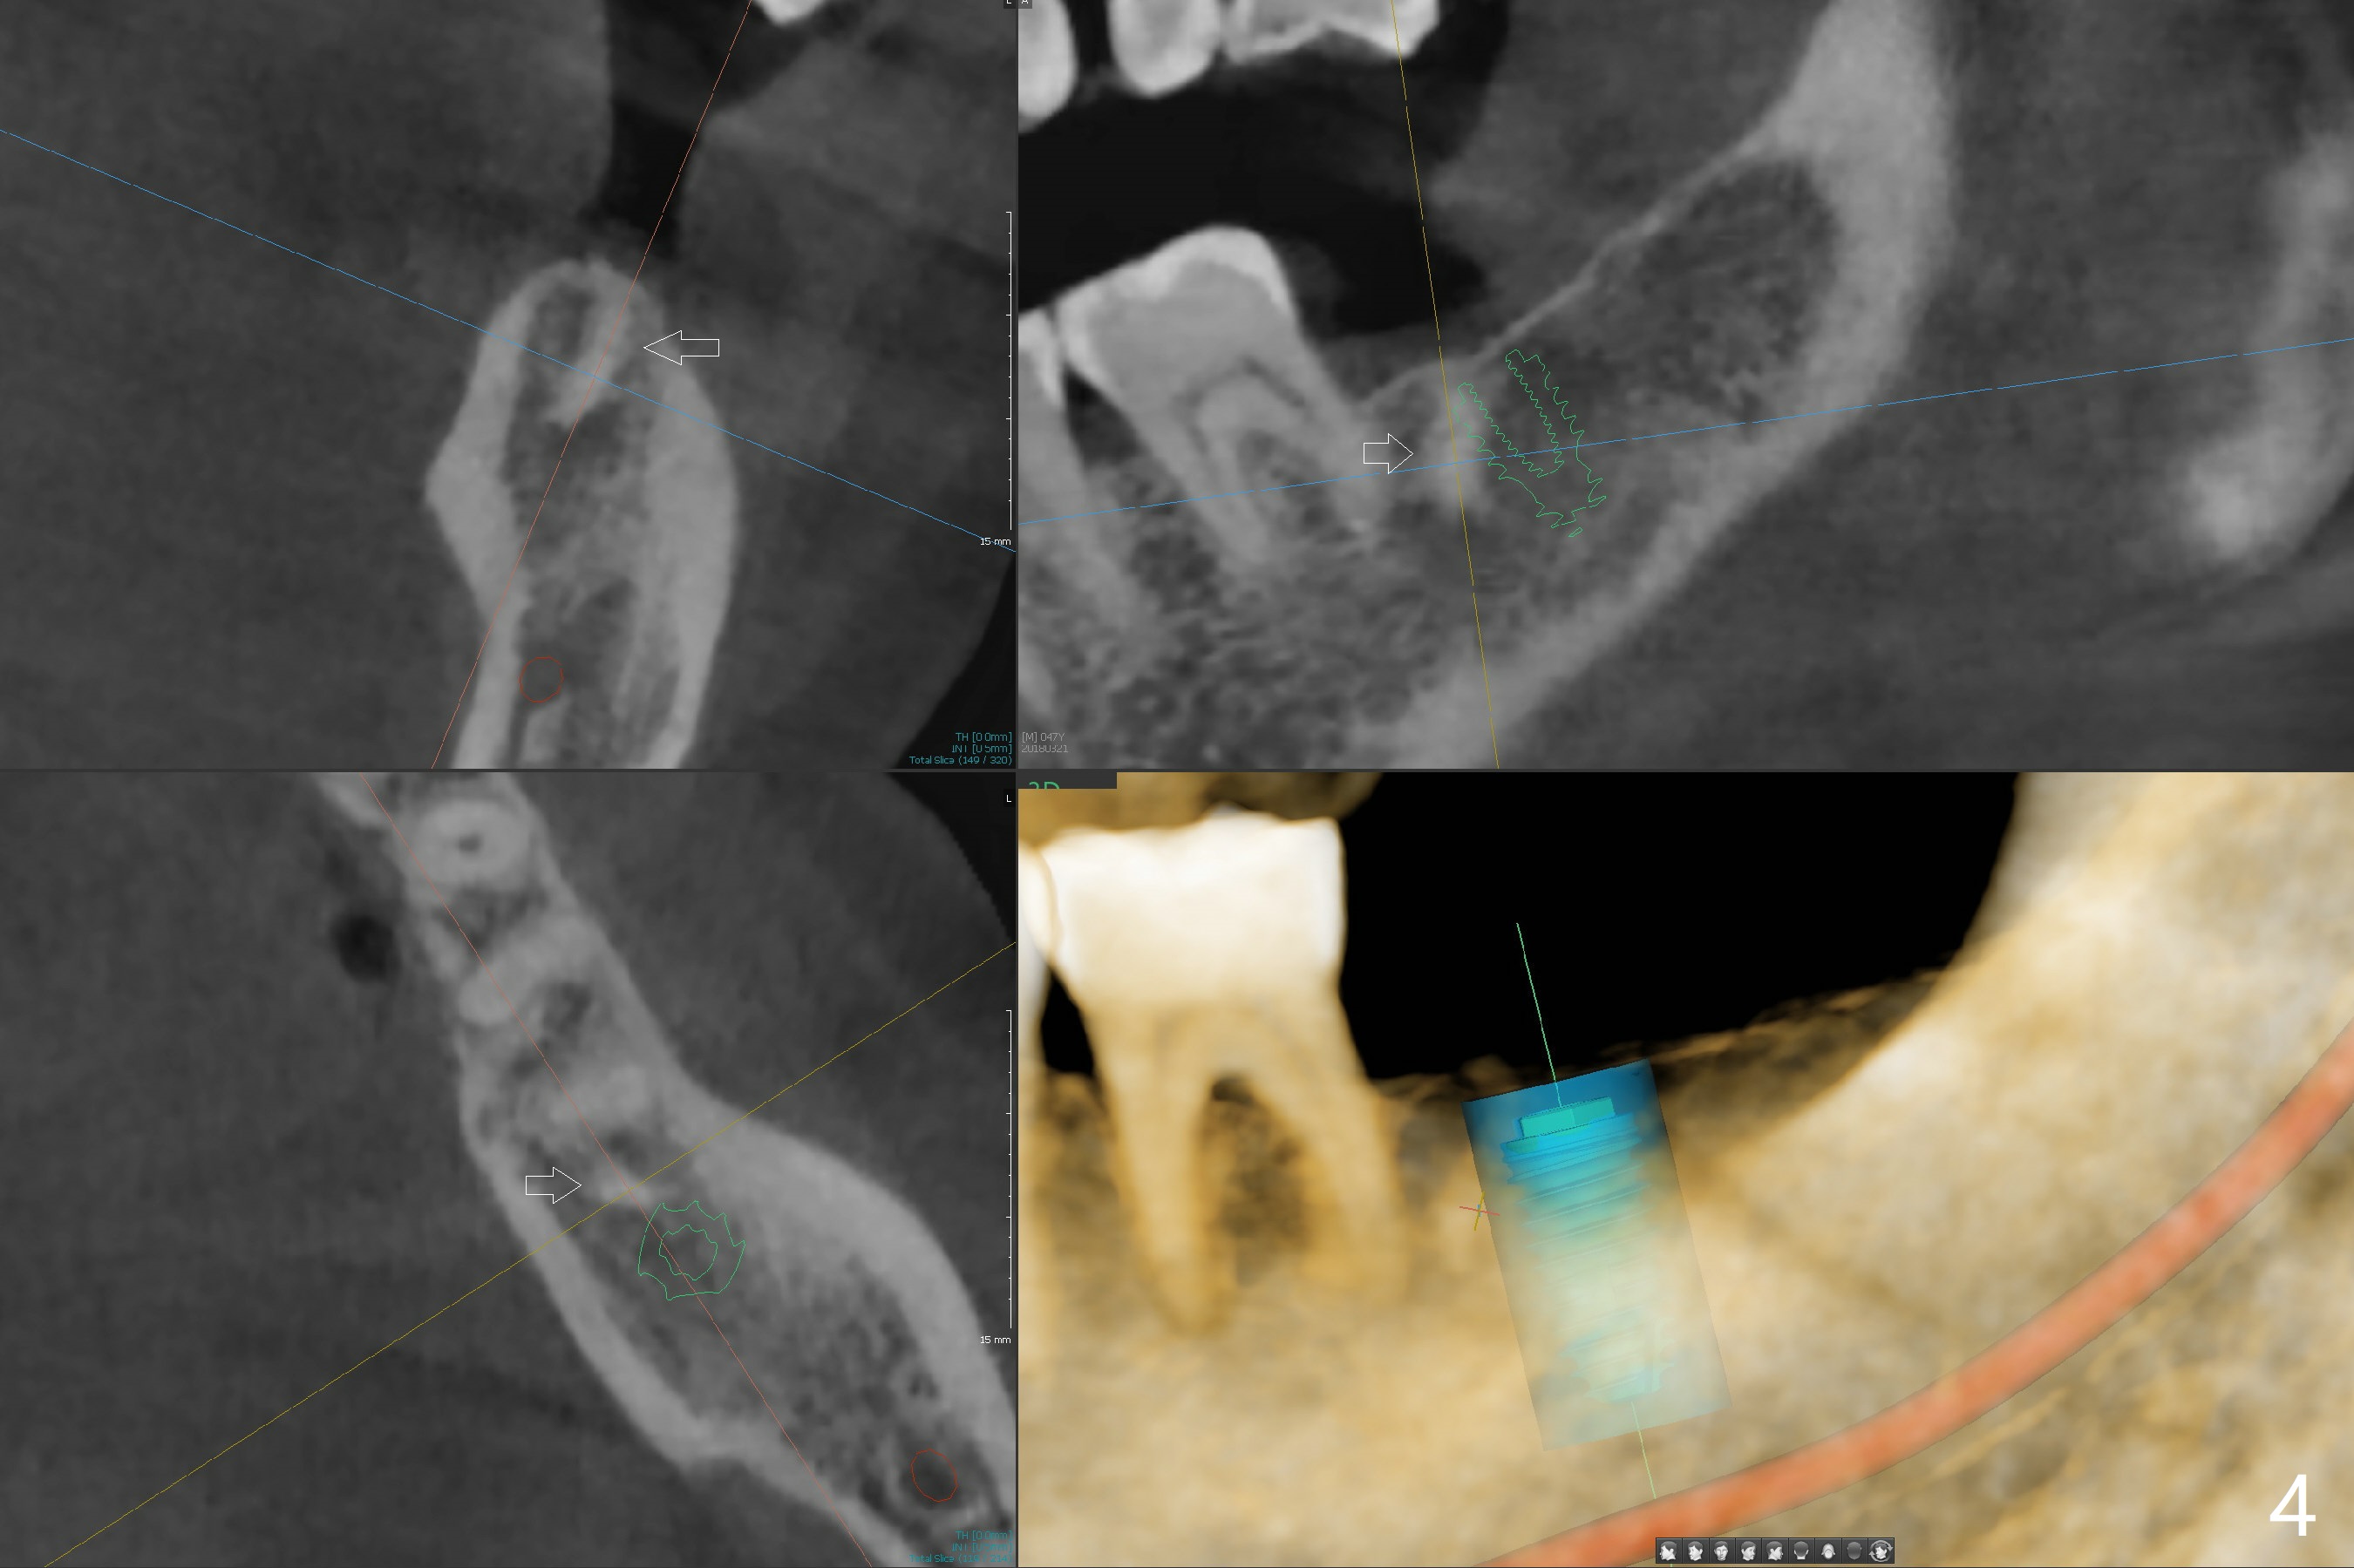

Dense Bone or Residual Root

There is a piece of radiopaque material in the mesial aspect at the site of #18 (Fig.3,4 arrow). After osteotomy and before implant placement, remove the guide to check whether it is dense bone or residual root. Prepare root tip picks. Encourage good oral hygiene (water pik) and postop antibiotic, since he is a diabetic.